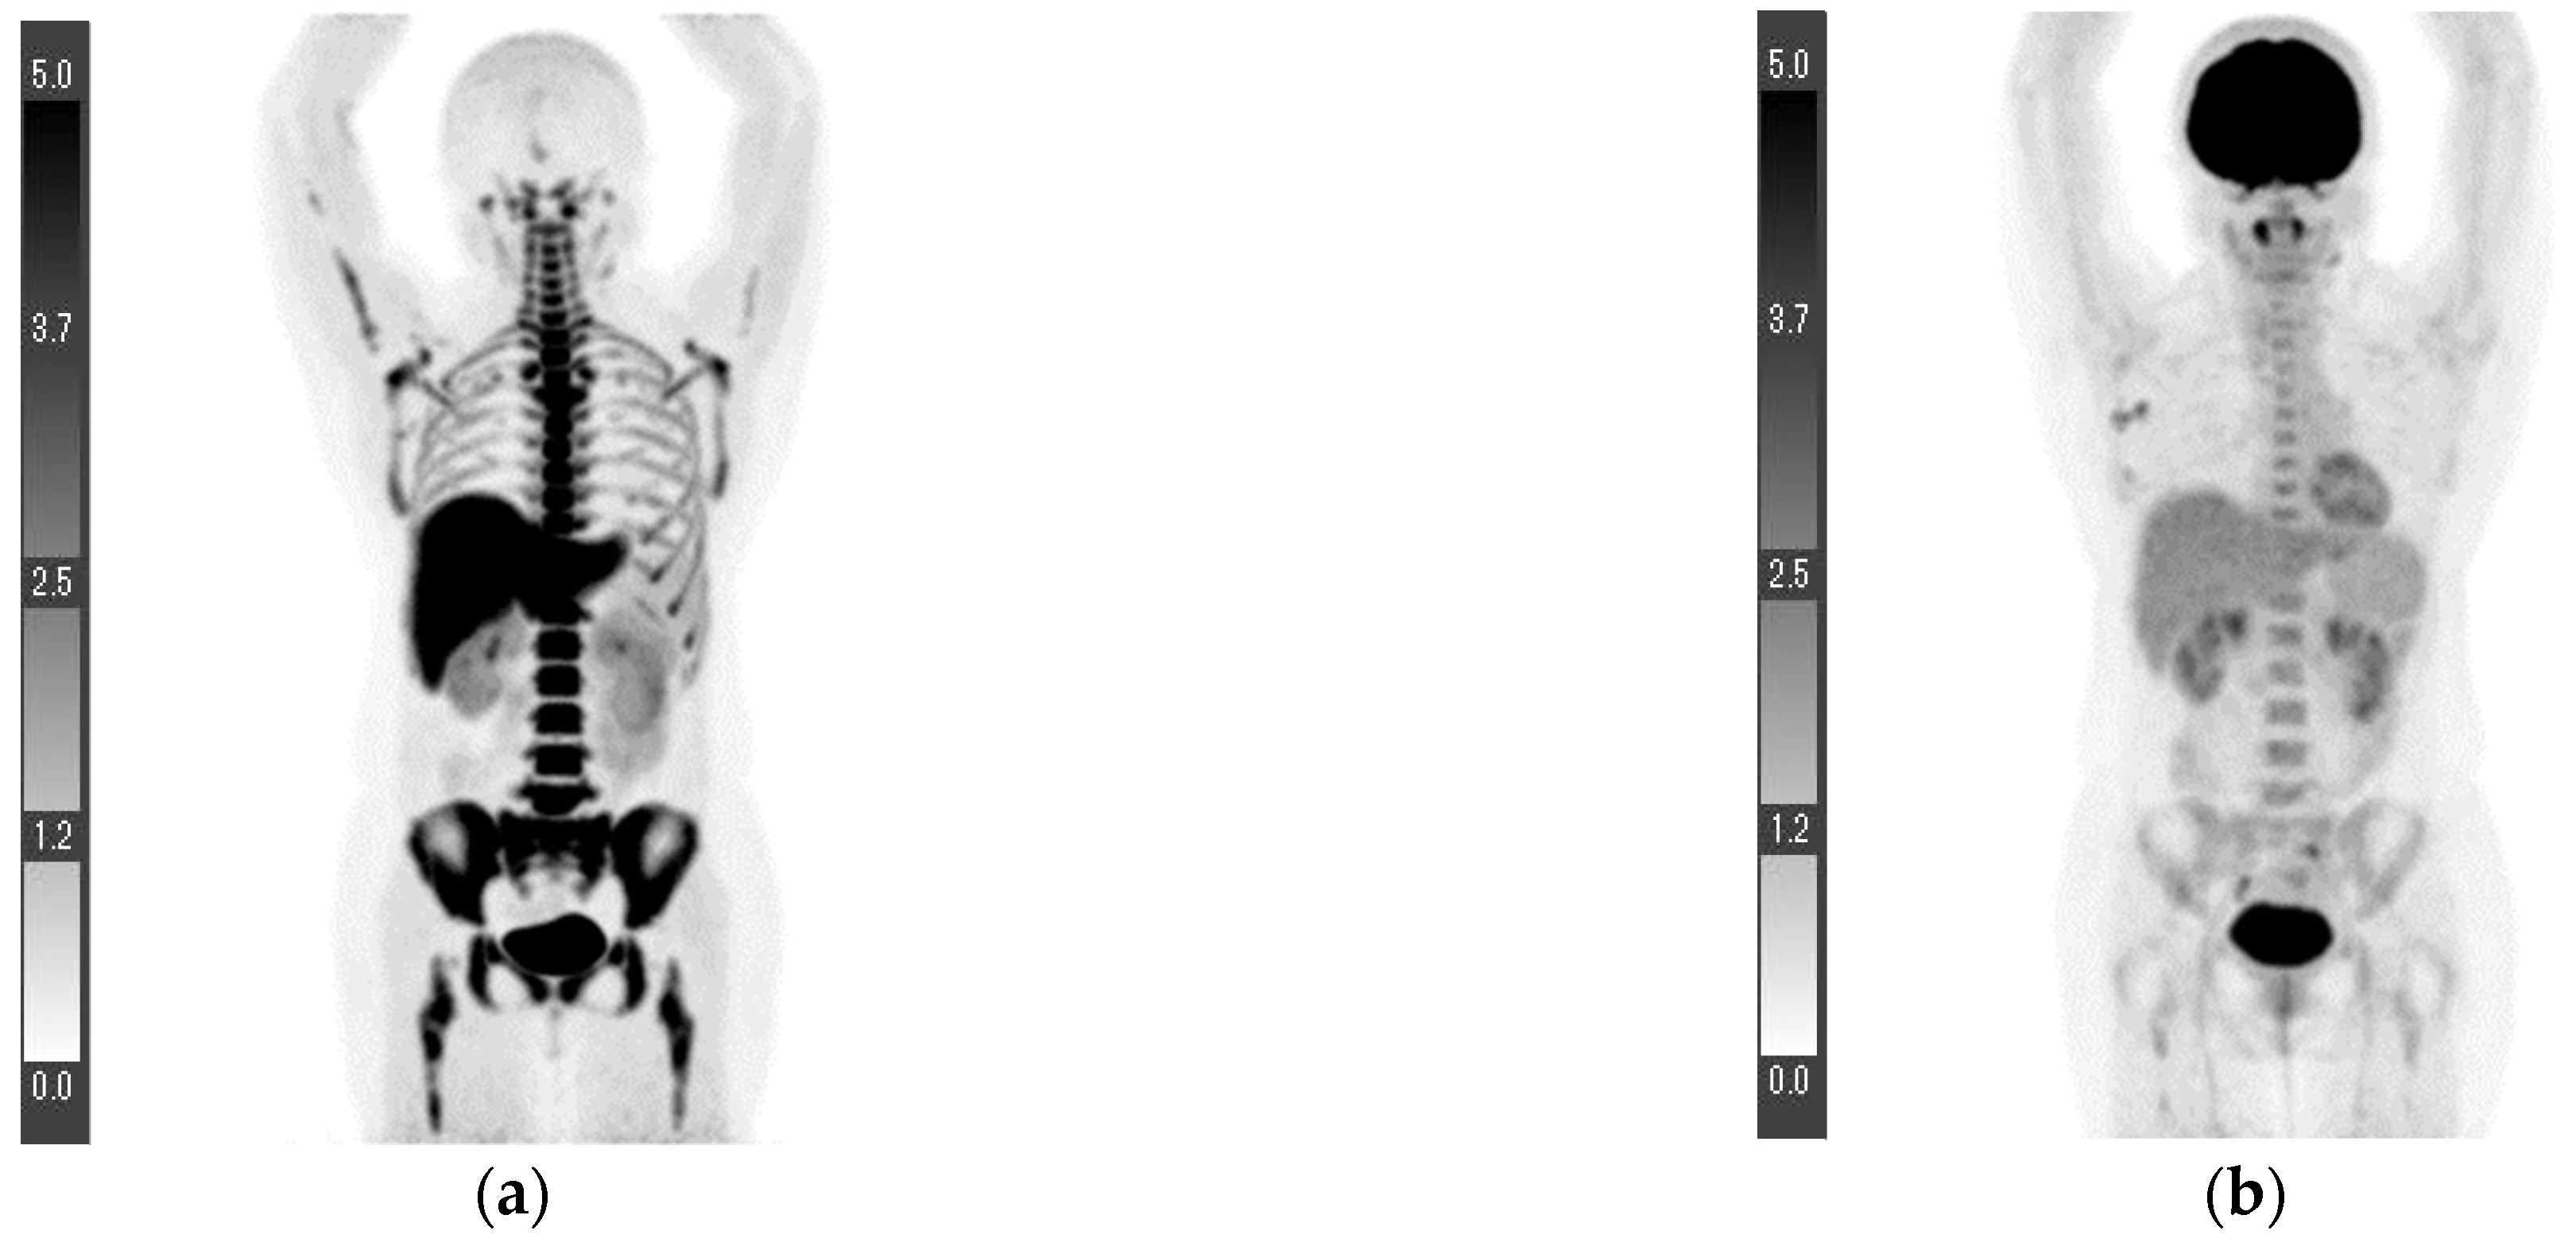

| 1 | 1.0 | 1.8 | 1.6 * | 3.4 * | T1cN2aM0 ** | Invasive ductal carcinoma | 1 | + | + | − | 1.0 |

| 2 | 0.6 | 1.6 | 0.7 | 0.8 | T1bN0M0 ** | Invasive ductal carcinoma | 1 | + | + | − | 6.7 |

| 3 | 2.2 | 3.1 | 0.5 | 0.6 | T1cN0M0 ** | Invasive ductal carcinoma | 2 | + | + | − | 24.6 |

| 4 | 0.4 | 1.5 | 16.7 * | 14.2 * | T1bN3aM1 *** (Lymph node and bone metastases) | Invasive ductal carcinoma | Data loss | + | + | − | Data loss |

| 5 | 3.8 | 8.3 | 1.8 | 6.3 | T2N3bM0 *** | Invasive ductal carcinoma | 1 | + | + | − | 25 |

| 6 | 4.8 | 8.4 | 1.4 | 3.2 | T4bN1M1 *** (Lumbar vertebra metastasis) | Invasive ductal carcinoma | 1 | + | + | − | 8.9 |

| 7 **** | 7.0 | 10.1 | 1.2 | 0.7 | T4bN0M0 | Invasive ductal carcinoma | Data loss | − | − | + | 59 |

| 8 ***** | - | - | 1.1 | 4.1 | N3bM1 (Lymph node, lung, and bone metastases) | Invasive ductal carcinoma | 3 | + | − | + | 29.3 |